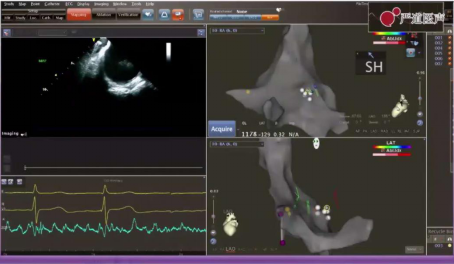

手术由龙德勇教授完成,患者为青年男性,诊断为阵发性房颤,采用零射线射频消融技术,超声+Pentaray技术。房颤患者零射线消融中,首先是三维建模,右房内穿刺房间隔,50W功率行肺静脉隔离消融,消融点与点距离5mm左右,术后患者由持续房颤恢复窦性心律。零射线射频消融技术学习曲线较短,但是手术时间较长,需要术者具有丰富的临床经验。

超声+Pentaray技术